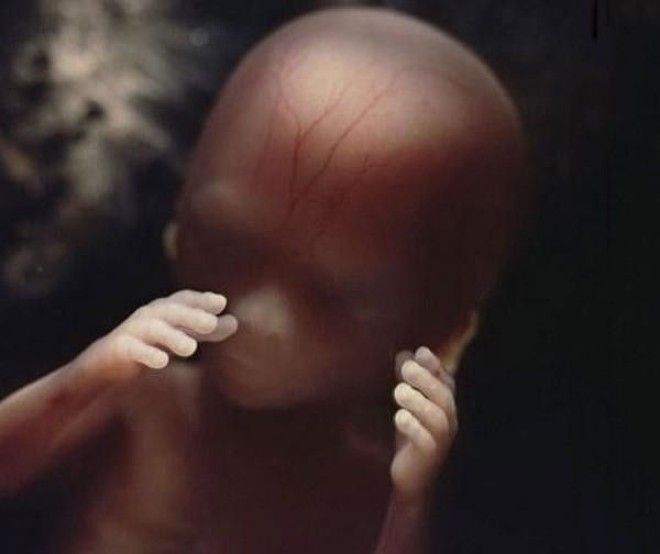

Сквозь тонкую кожу видна сеть кровеносных сосудов

18 недель. Зародыш может воспринимать звуки из внешнего мира